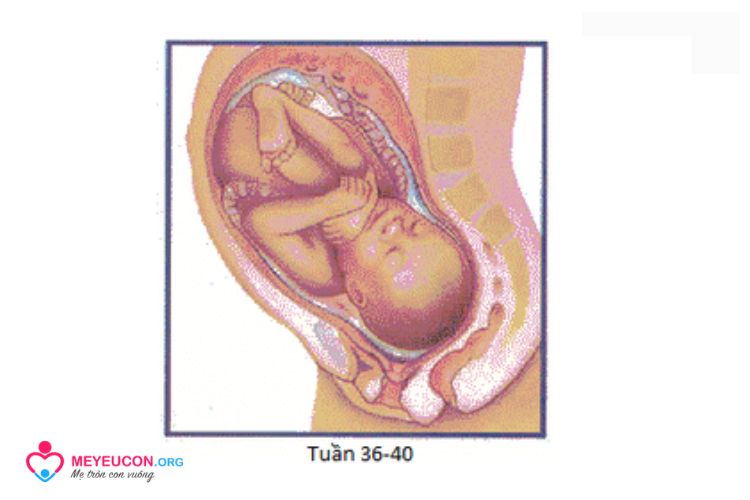

Tuần 36-40

Chiều dài từ 34 đến 50 cm, có thể nặng từ 2948 g đến 4535 g

Phổi thường trưởng thành. Thai nhi có thể nắm khá chắc. Thai nhi biết hướng về phía nguồn sáng. Trẻ có 99% cơ hội sống sót khi được chăm sóc trẻ sơ sinh phù hợp.

Đến đây thì bé đã sẵn sàng để nằm trong vòng tay yêu thương của bạn và gia đình rồi. Hãy chuẩn bị đồ để đi sinh bạn nhé!